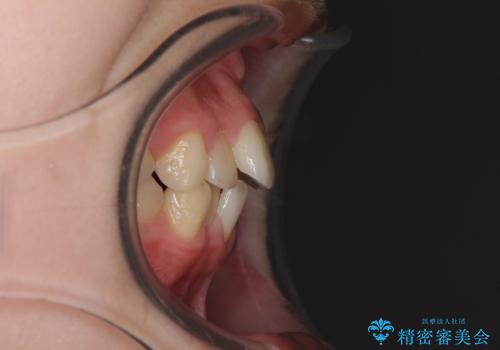

乳歯が3歯残っており、下顎は左右ともに後続永久歯がない状態でした。

口元が突出しており、口が閉じにくかったため、乳歯を含め上下5歯を抜歯して矯正治療を行うこととしました。

下顎の乳歯は永久歯と比べて幅が大きいため、抜歯した場合のスペースが大きく、治療には長期間を要することが一般的です。